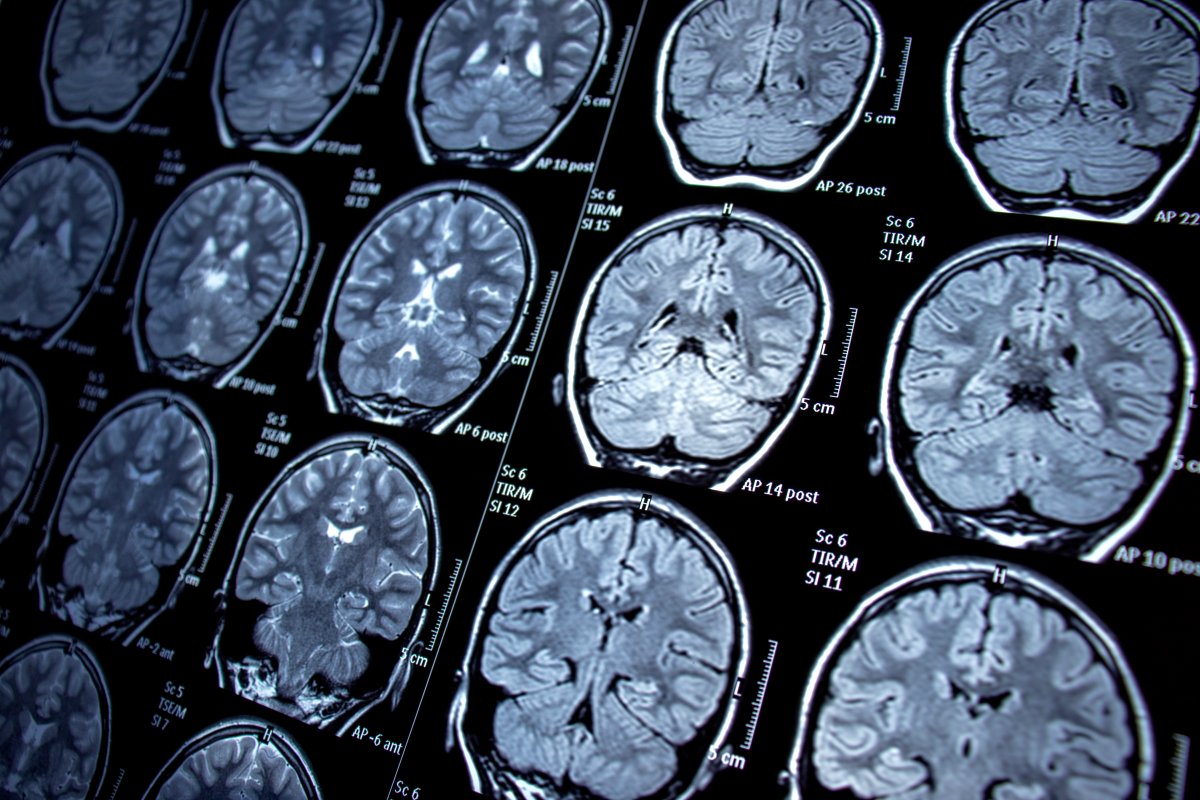

According to a Middlesex-London Health Unit Infection Prevention and Control Lapse disclosure report from Nov. 24, 2023, Rice is a neurologist who operated a home-based clinic.

The complaints centred on the improper use of multi-dose vials and the improper reprocessing of multi-use instruments used in neurological examinations.

If you received a procedure from Rice between 2019 and last September, you are asked to contact a health-care provider for precautionary testing. Procedures include injections, lumbar punctures and bone marrow biopsies.